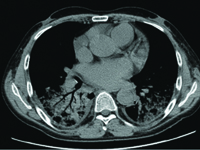

Patients with chronic renal failure, after kidney transplantation, have an increased risk of developing of tuberculosis. The clinical and radiological picture of tuberculosis in immunosuppressed patients is uncharacteristic, often suggestive of another disease process. The increased risk of generalization of the disease and the significant proportion of deaths in this group of patients prompts a thorough diagnosis of mycobacterium tuberculosis infection.